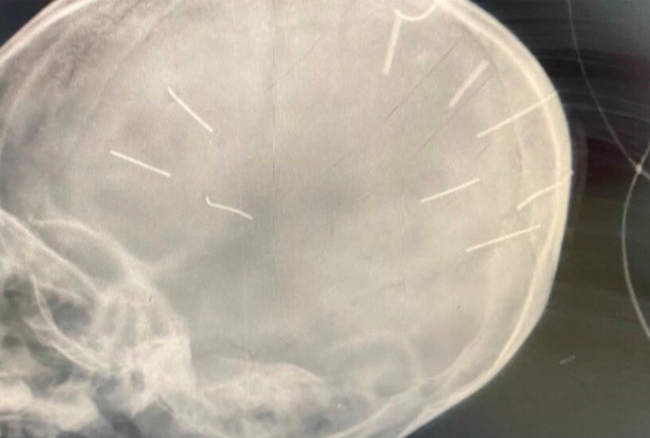

Tại đây, sau khi tiến hành chụp X-Quang, các bác sĩ Bệnh viện Đa khoa huyện Thạch Thất phát hiện trên sọ bé A. có nhiều vật thể giống đinh găm bên trong, tổng cộng 9 chiếc, trên đầu có chút sưng tấy.

9 vật giống đinh găm vào sọ bé A.